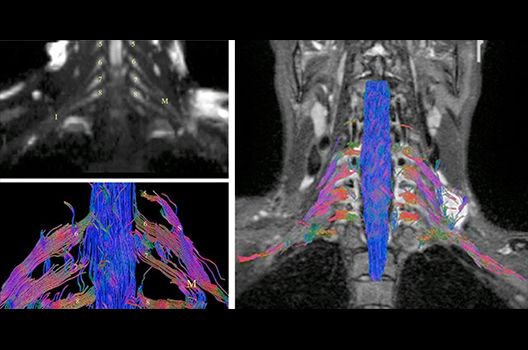

- MR-Diffusionstensorbildgebung (Faserbahndarstellung/fiber tracking)

Die Schwerpunkte in der MR-Forschung liegen in der multiparametrischen und funktionellen Bildgebung bei onkologischen und anderen, neuroradiologischen Fragestellungen und umfassen die Anwendung modernster MR-Verfahren sowie die Untersuchung an Hochfeld-Geräten.

Die Magnetresonanztomographie (MRT) ist ein Verfahren, bei dem durch magnetische Kräfte Bilder des Körperinneren angefertigt werden. In der Neuroradiologie können manchmal kleinste Veränderungen schwere Folgen haben; daher forschen wir an der Entwicklung hochauflösender MRT-Sequenzen, mit denen diese Prozesse und auch einzelne Nervenfaserbahnen sichtbar gemacht werden können. Darüber hinaus sind bei vielen Erkrankungen des Gehirns die Blutgefäße betroffen. Daher arbeiten wir an der Neu- und Weiterentwicklung von MRT-Sequenzen zur Darstellung der Blutgefäße und zur Blutflussanalyse (sog. „Angio-MRT“). Einen besonderen Forschungsschwerpunkt unserer Klinik stellen die MR-Protonenspektroskopie und die funktionelle MRT dar, mit denen die Analyse einzelner chemischer Substanzen im Hirngewebe oder die Darstellung ausgewählter Hirnfunktionen möglich ist.